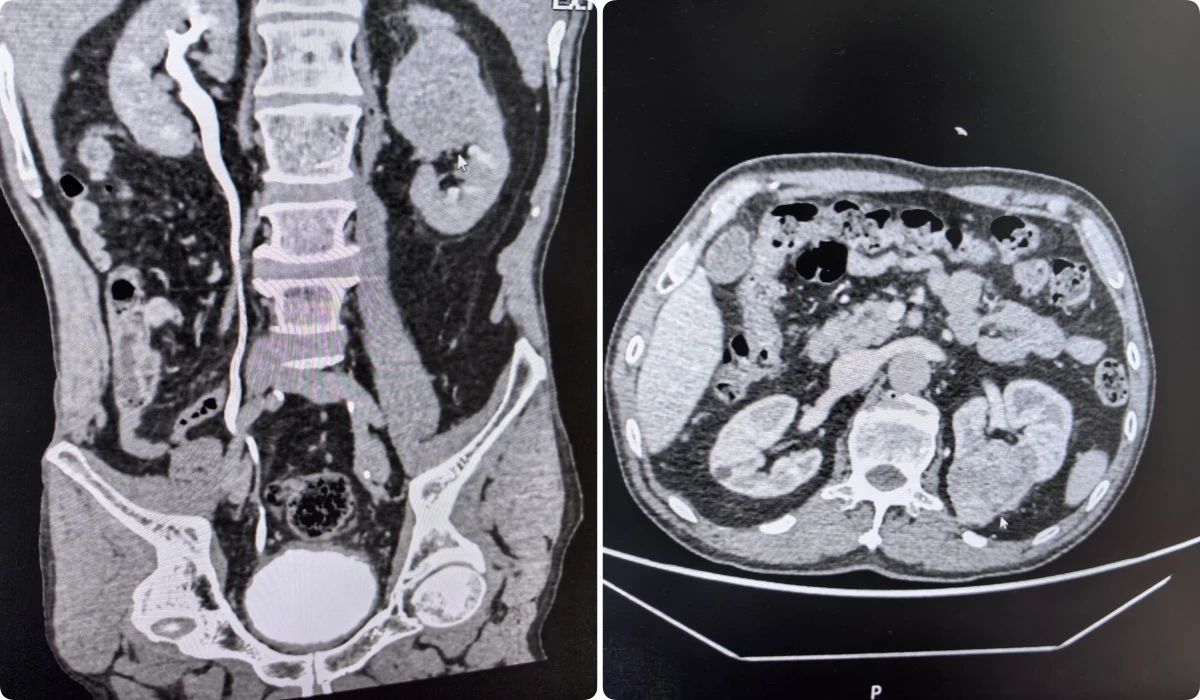

病例1:一位因排尿困难就诊的患者,在细致检查后被确诊为右肾占位性病变(倾向恶性),并伴有前列腺增生。面对复杂病情,我院泌尿外科团队在充分术前评估与多学科会诊的基础上,精心制定了分阶段治疗方案。首先解决患者排尿难题,随后择期实施了腹腔镜下肾根治性切除术,实现了对病灶的精准切除。患者术后恢复良好,生活质量得到提升。病例2:患者因右侧肾盂结石反复泌尿道感染,经抗炎治疗效果不佳。泌尿外科团队决定采用经尿道输尿管软镜肾盂激光碎石取石术,手术成功,感染得到控制。病例3:患者因“尿频、夜尿增多”来院拟行前列腺手术。入院进一步CT检查发现左肾肿瘤、考虑恶性。团队经充分评估,行腹腔镜下肾根治性切除术。病例4:一例无痛性肉眼血尿患者,经增强CT确诊输尿管占位性病变后,行腹腔镜下左侧肾输尿管全长及部分膀胱切除术。腹腔镜下肾切除术有什么优势呢?